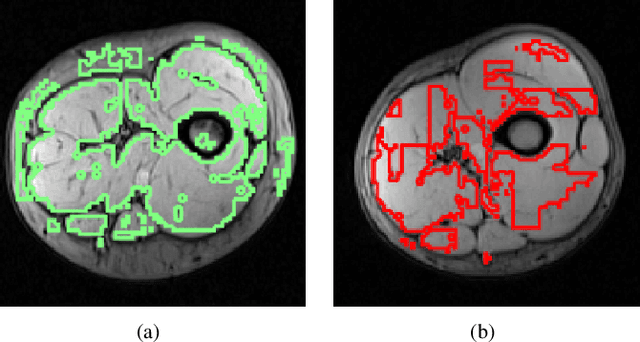

Abstract:Segmentation of skeletal muscles in Magnetic Resonance Images (MRI) is essential for the study of muscle physiology and diagnosis of muscular pathologies. However, manual segmentation of large MRI volumes is a time-consuming task. The state-of-the-art on algorithms for muscle segmentation in MRI is still not very extensive and is somewhat database-dependent. In this paper, an automated segmentation method based on AdaBoost classification of local texture features is presented. The texture descriptor consists of the Histogram of Oriented Gradients (HOG), Wavelet-based features, and a set of statistical measures computed from both the original and the Laplacian of Gaussian filtering of the grayscale MRI. The classifier performance suggests that texture analysis may be a helpful tool for designing a generalized and automated MRI muscle segmentation framework. Furthermore, an atlas-based approach to individual muscle segmentation is also described in this paper. The atlas is obtained by overlaying the muscle segmentation ground truth, provided by a radiologist, after image alignment using an appropriate affine transformation. Then, it is used to define the muscle labels upon the AdaBoost binary segmentation. The developed atlas method provides reasonable results when an accurate muscle tissue segmentation was obtained.